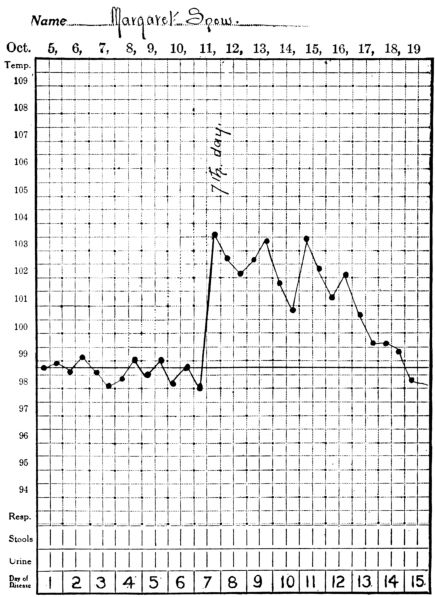

| 3. | Showing temperature curve in streptococcus infection | 397 |

| 4. | Showing temperature curve in gonorrhœal infection | 398 |